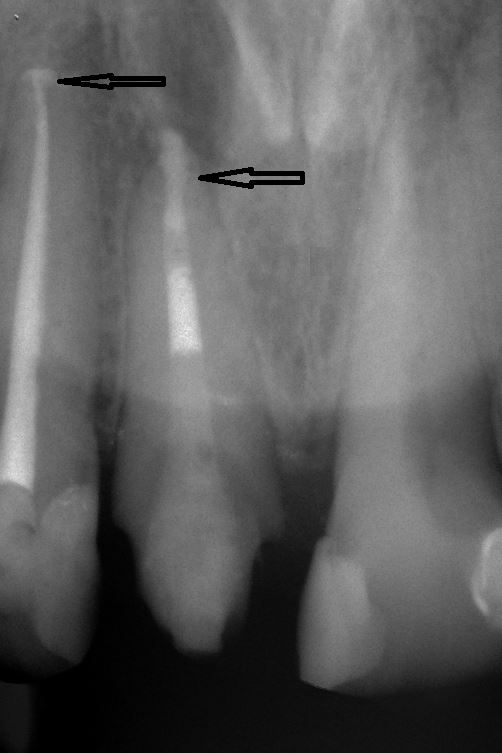

Fallbeispiel für einen Seitenrand

Fallbeispiel für einen komplexen Kanalverlauf

Fallbeispiel für eine große Entzündung an der Wurzel

Wurzel nach erfolgreicher Behandlung 2 Monate später schon fast ausgeheilt

Fallbeispiel für eine unvollständige Wurzelfüllung

nach Revision und dichtem Verschluss